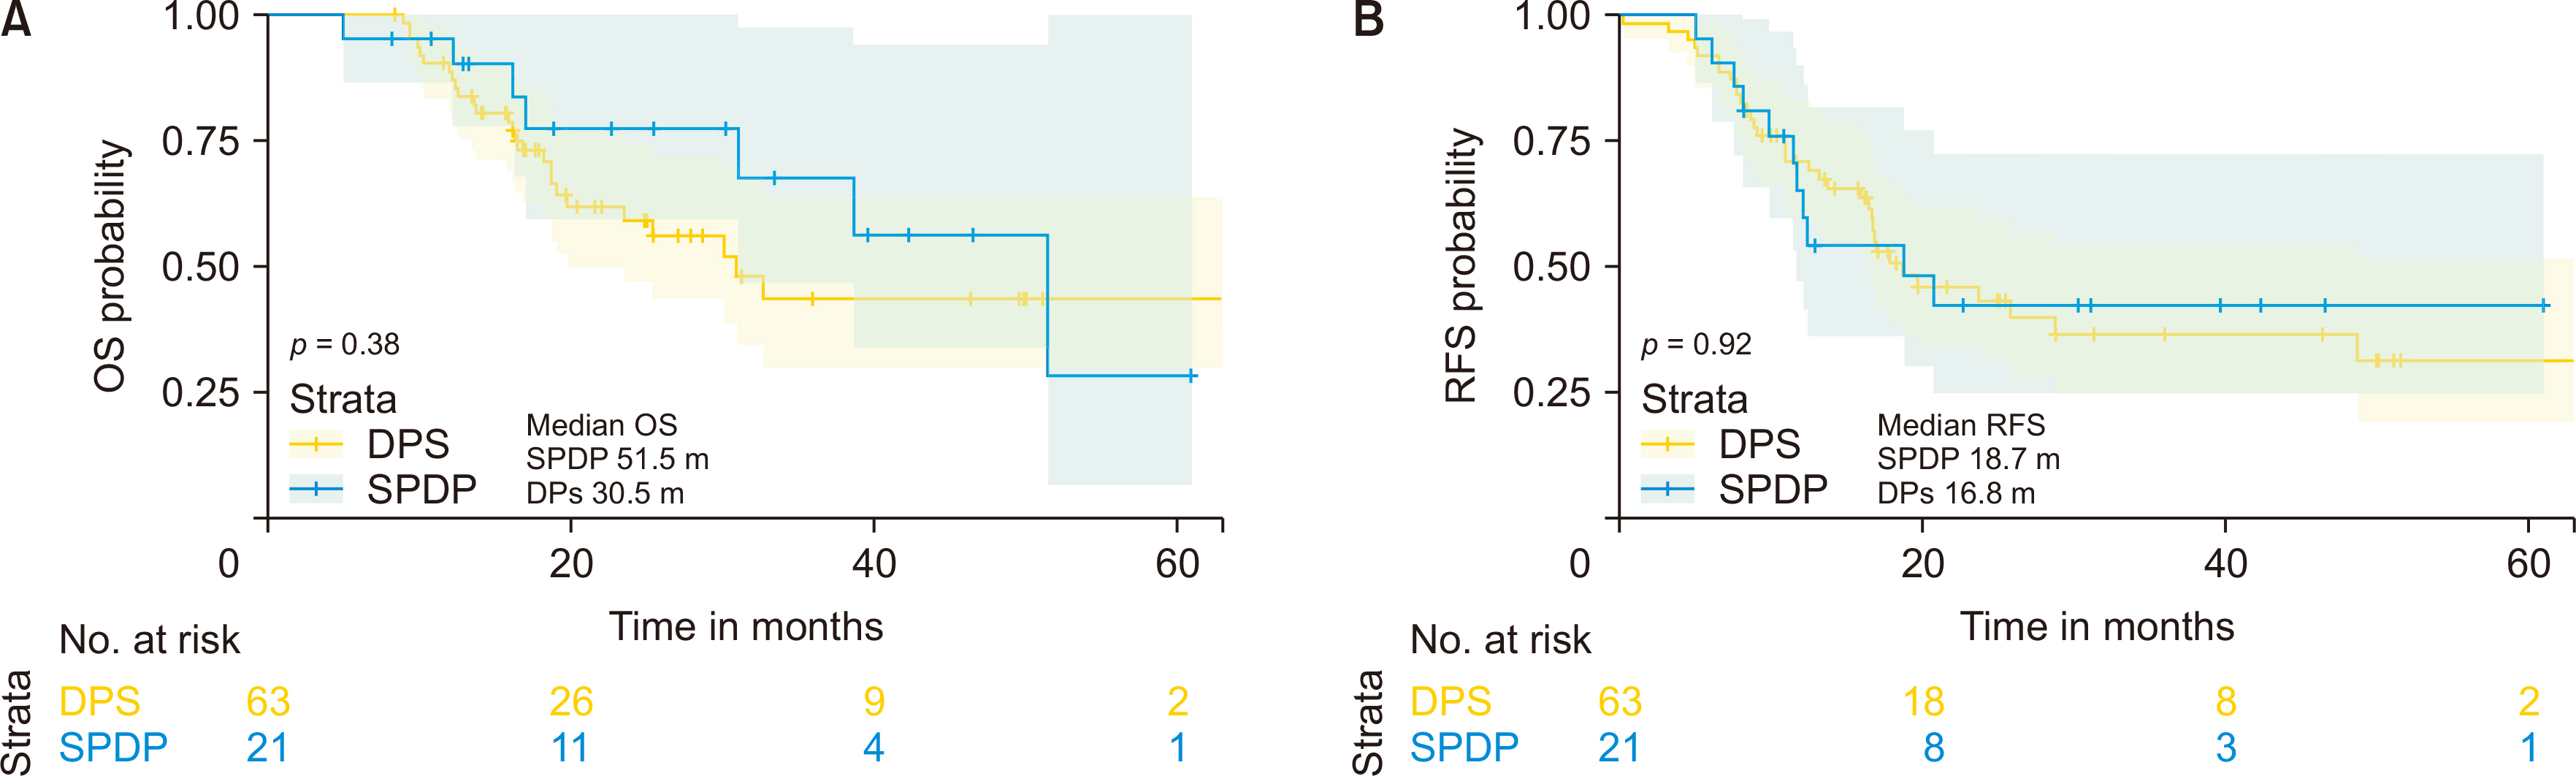

Both groups exhibited similar demographic, intraoperative, and pathological characteristics, with the exception of a reduced number of total lymph nodes (p = 0.006) in the SPDP group. There were no significant differences in the rates of postoperative complications, recurrence, or metastasis. Local recurrence predominantly occurred in the central region as opposed to the spleen region. There were no cases of isolated recurrences in the splenic region. Median overall survival and recurrence-free survival times were 51.5 months for SPDP vs 30.5 months for DPS and 18.7 months vs 16.8 months, respectively (p > 0.05). The incidence of partial splenic infarction and left-side portal hypertension in the SPDP group was 28.6% (6/21) and 9.5% (2/21), respectively, without necessitating splenic abscess puncture, splenectomy, or causing bleeding from perigastric varices.